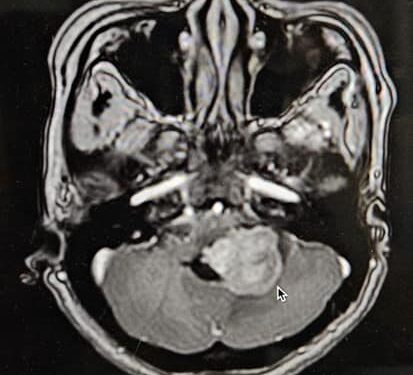

Ngày 19/5/2024, Bệnh viện Đa khoa tỉnh Khánh Hòa đã phẫu thuật thành công cho một bệnh nhân bị u não Ependymomas tiểu não. Bệnh nhân Đ.T.T.T (42 tuổi, Ninh Hòa) nhập viện với triệu chứng đau đầu và yếu nửa người trái. Qua quá trình khám và chụp MRI, bác sĩ phát hiện khối u ở tiểu não trái kích thước 25x30x35mm, gây chèn ép vào các cấu trúc não xung quanh. Sau khi được tư vấn, bệnh nhân đồng ý tiến hành vi phẫu thuật để lấy khối u và gửi đi giải phẫu bệnh.

Bệnh nhân được các bác sĩ Khoa Ngoại Thần kinh Bệnh viện Đa khoa tỉnh Khánh Hòa thực hiện, với sự hỗ trợ của TS.BS. Đỗ Hồng Hải – Chuyên gia phẫu thuật thần kinh từ Bệnh viện Đại học Y Dược TP Hồ Chí Minh. Ca phẫu thuật đã được thực hiện thành công sau 4 giờ, khối u được lấy hoàn toàn và bệnh nhân cải thiện rõ rệt các triệu chứng đau đầu, yếu nửa người chỉ sau 2 ngày. Kết quả giải phẫu bệnh xác nhận đây là u não Ependymomas tiểu não.